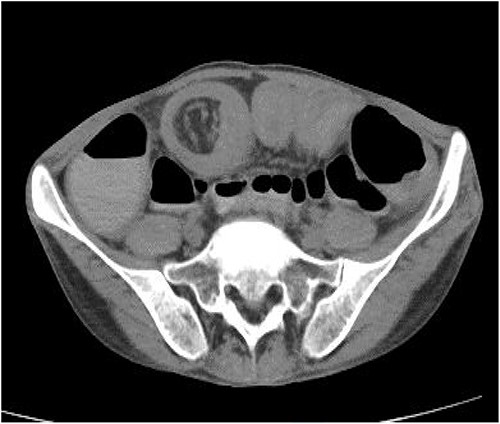

Blood tests, a 12-lead electrocardiogram, a chest X-ray and an abdominal X-ray were conducted in light of the ongoing abdominal pain, but the results were unremarkable. Additionally, pre- and post-contrast CT of the pelvis and abdomen was performed in a variety of planes and settings. After administering oral and intravenous contrast, it was seen that the proximal small bowel loops were dilated along with an ileo-ileal intussusception in the midline in the hypogastric region and jejuno-jejunal intussusception in the lumbar region. Figure 1 shows a CT coronal picture of the abdomen and pelvis that illustrates an intussusception and dilated loops. A spherical mass referred as ‘target-like lesion/donut-like lesion’, which is indicative of intussusception, is also seen in the CT axial image as seen in Fig. 2.

CT axial image showing a spherical mass referred as ‘target-like lesion/ donut-like lesion’, indicative of intussusception.